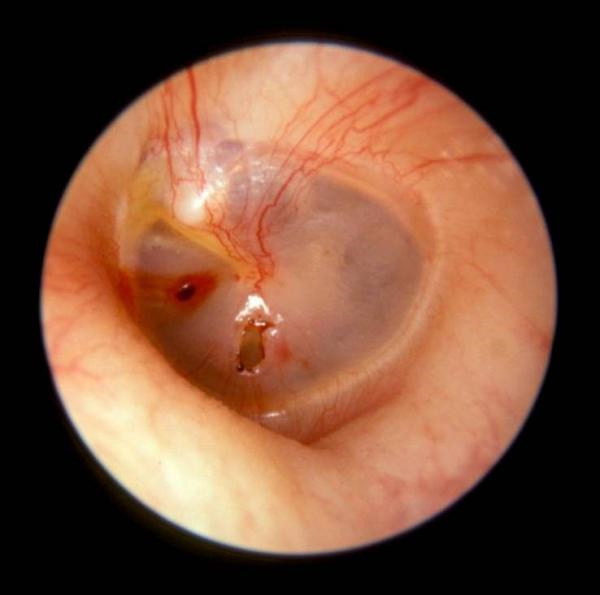

住院治療鼓膜穿孔